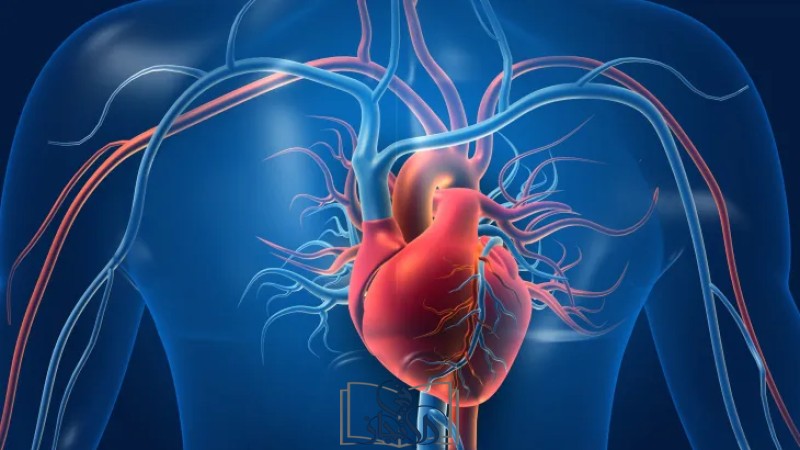

يُعد قصور القلب من الأمراض المزمنة التي تؤثر بشكل كبير على جودة حياة المريض، ويحدث عندما يصبح القلب غير قادر على ضخ كمية كافية من الدم لتلبية احتياجات الجسم من الأوكسجين والغذاء، يمكن أن يتطور قصور القلب تدريجيًا نتيجة أمراض مزمنة مثل ارتفاع ضغط الدم أو السكري أو أمراض الشرايين التاجية، ويُسبب هذا القصور تراكم السوائل في الجسم مما يؤدي إلى تورم في القدمين وضيق في التنفس، ويحتاج المريض إلى متابعة دقيقة ونظام علاجي متكامل يشمل الأدوية وتغييرات في نمط الحياة لتقليل الأعراض وتحسين الوظائف الحيوية للقلب.

أنواع قصور القلب وتأثير كل منها

ينقسم قصور القلب إلى أنواع حسب الجهة المصابة أو وظيفة القلب

قصور في الجانب الأيسر يؤدي إلى احتقان الرئتين وضيق التنفس

قصور في الجانب الأيمن يسبب تورم الأطراف وتجمع السوائل بالبطن

قصور القلب الانقباضي يحدث عندما تكون عضلة القلب ضعيفة في الضخ

قصور القلب الانبساطي يحدث عند عدم امتلاء القلب بالدم بشكل كافٍ